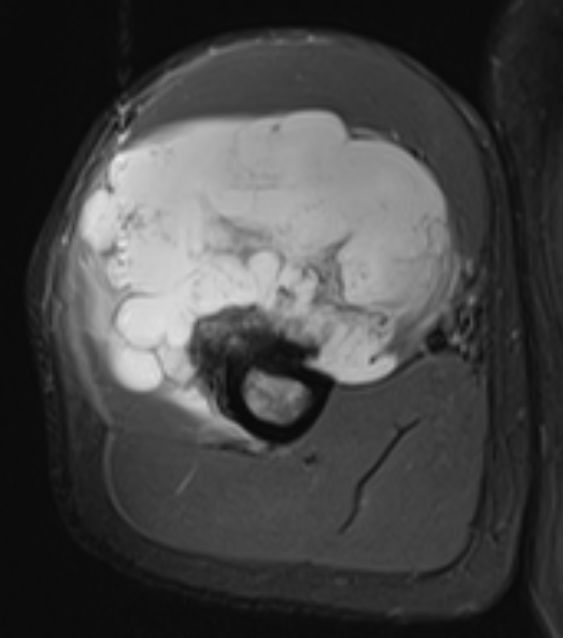

MRI

- MRI of 179 chondrosaroma

- features of high grade chondrosarcoma

- bone expansion, active periostitis, soft tissue mass and increased tumour length